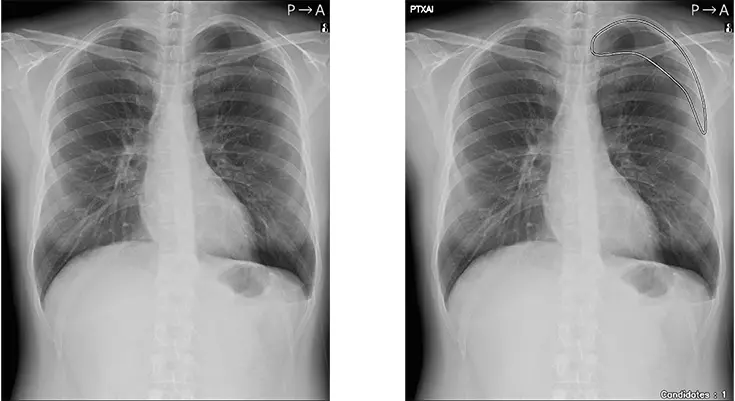

「CXR Finding-i 気胸検出タイプ」は、胸部単純X線画像をAI※2で解析することで重要所見である気胸の候補を迅速に検出し、候補領域を画像上に表示することで見落とし防止を支援します。病変検出性能を示す指標である感度※3は95%と高い水準を実現していることに加え、気胸が存在しない画像をAIが正しく陰性(気胸なし)と判断した割合を示す特異度※4は96%であり、病変を見逃さないようにしつつ偽陽性も抑制した高精度の検出性能が特長です。

人のレントゲン写真 オリジナル画像

オリジナル画像

人のレントゲン写真 気胸の検出領域を表示

気胸の検出領域を表示